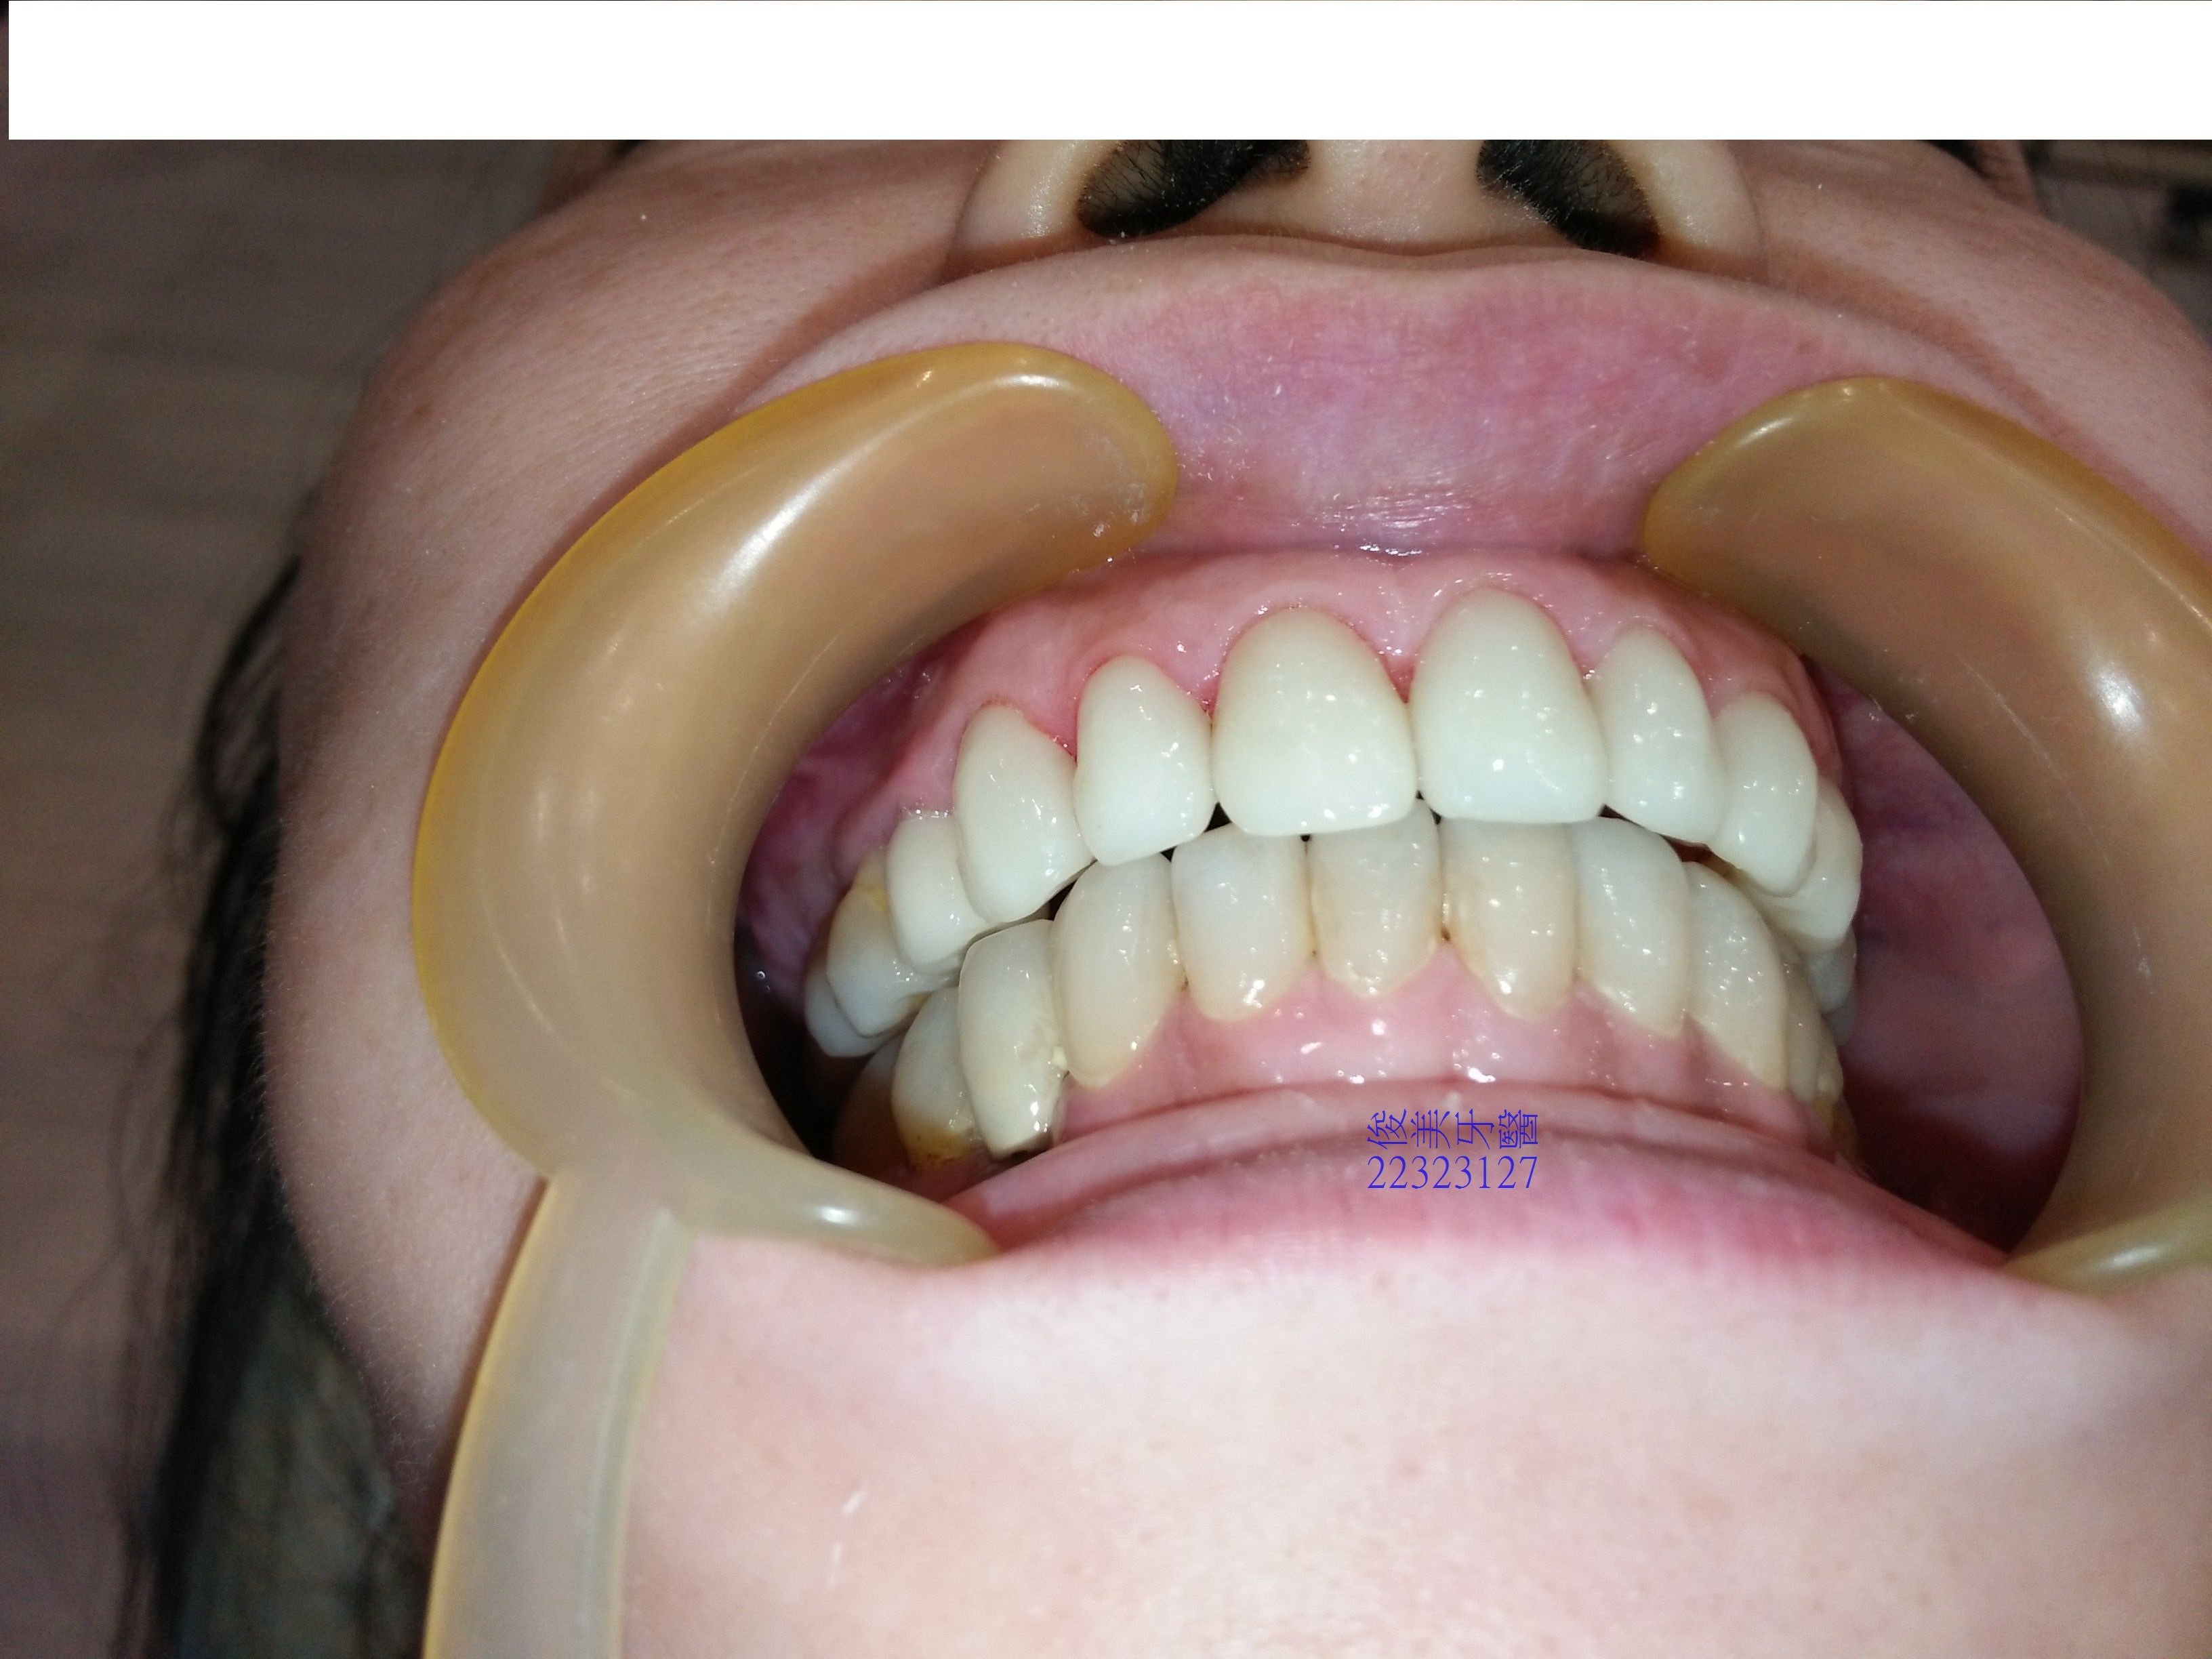

全部療程結束了,不但建立後牙高度,前牙對稱和美學,以及患者想要的美白效果都達成了。

將患者原本輕微臉型歪歪的問題解決了,恢復良好不干擾的咀嚼功能,也避免前牙磨損惡化的問題。

前牙獲得保護、也擁有美觀。

專利設計,不修磨過多琺瑯質,保留牙齒活性,不需抽神經,延長牙齒使用年限。

好清,比自然牙更不容易堆積食物染色,美觀更持久。